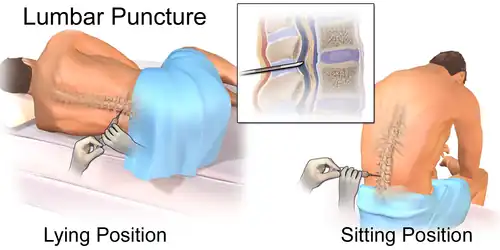

- Lumbar puncture to measure neurofilament light protein (NFL) in the cerebrospinal fluid (CSF) to follow the progression of the disease[12]. An increase NFL level on CSF examinations may suggest faster disease course as well as a worse prognosis.[12]